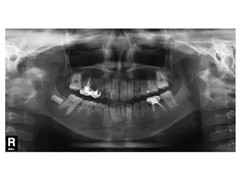

恒齿上头的骨头每减少1mm约需要6个月的时间,那么如何判断是否需要空间保持器?X光片上看恒齿上骨头的覆盖量有没有1mm,如果片子模糊无法判断,可以先将乳牙拔掉,看伤口的洞里是否有恒牙萌出,如果有就不用做。

图示口腔中有很多先天缺牙的情况,因此考虑先天缺牙的部分需要进行种植。